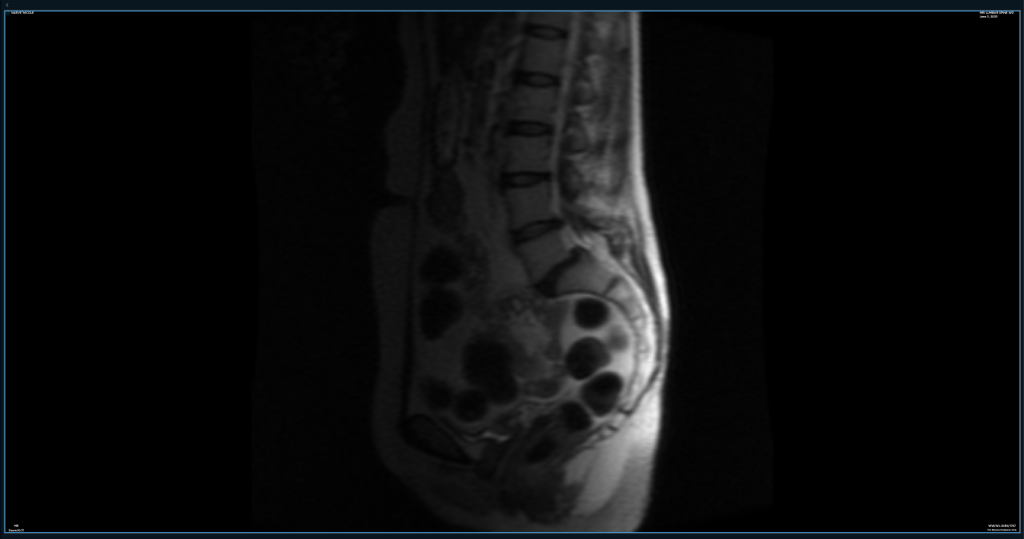

The Spine

I spent many hours in an MRI machine these past few months, for the fresh information and to get in the door with various specialists. I’ve had imaging of my pelvis and entire spine, and a brain MRI is upcoming. Pro tip: I upload all my imaging (when it works) to an online service, where it’s accessible and I can loop in docs with a simple email address (when they’re willing, which is maybe 50% of the time.) In any case, it keeps it all organized. I currently use MyMedical Images.com.

To sum up, there’s basically something – um, nefarious? – going on at about every level of my spine. The radiologist’s report is a thick jabberwocky of terms I stopped hi-lighting because the whole page was bleeding yellow. Things like “severe bilateral stenosis” stand out among several mentions of “bulging,” “thickening,” “pars defects,” “anterolisthesis” and my favorite word to say, “spodylolisthesis.” (“LOL” is right there in the word!) There’s also “kyphosis,” and many, many mentions of “protrusions” and “osteophytes” and “narrowing.” A scoliotic curve rounds it all out nicely.

The one bit of good news I thought I had to share was the radiologist did not see evidence of CSF leak, chiari malformation or tethered cord (kinda big deal spinal anomalies more common in EDSers than others.) One of my docs has strongly suspected 2-3 of these in recent months, which was one reason for multiple stints inside the MRI machine.

Niki, after twelve years in the vascular compression world, you’ve learned by now that radiologists look for certain things, and specialists see other things, right?

Well…I sat down with the new images with a new-ish doc. She’s an EDS specialist and very familiar with all the fun things hEDS has to offer, especially the spinal ones. We sighed, and I said, “Well, at least there’s no sign of CSF leak, chiari or tethered cord, right?” And she looked at me like, “Oh, sweetie…”

She then pointed out where my brain may be hanging low in the skull (“chiari malformation,”) where my spinal cord is falling lower than it should be within the spinal canal (“tethered cord”) and reminded me I have all the symptoms of a CSF leak, and it rarely shows up on imaging. She also had to explain – again – how in normal people the dura is a little like treated leather, which holds all that juicy spinal fluid inside, but in EDSers it can be more like cheesecloth, making the multiple leaks too miniscule to see on imaging – but present, nonetheless.

This could change my predicted surgery trajectory 180 degrees – in order to prevent more damage to my spine, we may need to surgically “untether” the spinal cord, inject some blood patches to seal the leak(s,) and who knows what else to fix this. Vascular compression surgeries may have to wait (which is kind of what I was doing, anyway? That or being a chicken.)

“Oh, and see this part here, where your disks bulge posteriorly? That’s concerning to me, for, um, safety,” says the new-wish doctor. “Like if you were in a minor fender-bender, you could…” She makes a slashing motion across her neck with her hand. “You really have never seen an orthopedic spine specialist, in all these years?” Um, let me think about that. The file drawers in my head open. Colorado Springs? Flip-flip-flip…Maybe. Chicago? Flip-flip…Nope, I was still insured in Colorado when I lived there. New York? Flip… I don’t think so. It just was not a high priority, with everything else going on. For decades, I was sure there was something immunological going on. A parasite, an autoimmune disease…(I wasn’t wrong, but I wasn’t completely right, either.) Mental note to add an orthopedic spine specialist to the list. And not go bungie jumping any time soon.

So, several things could be going on with my spine. Some of these issues have been there for decades and I’m still standing, (literally,) so, like, no biggie. It was considered due to “hard living” before we knew I had hEDS. We could chalk some of it up to my 50+ years, but that’s really stretching it. More likely, my spine is very angry due to some combination of the loose ligaments associated with hEDS, being jerked around by the tethered cord, and possibly one of the genetic anomalies mentioned above.

To boot, this doc has noted my sacrum is “one for a case study,” in the abnormal way it curves, which naturally leaves my intestines in a bind (get it?) and isn’t playing nicely with the L-5 junction, not to mention my rectocele (prolapse at the perineum), at all. (Actually she thinks it may be L-6, as she suspects I have an extra vertebra, but now I’m boring you.)